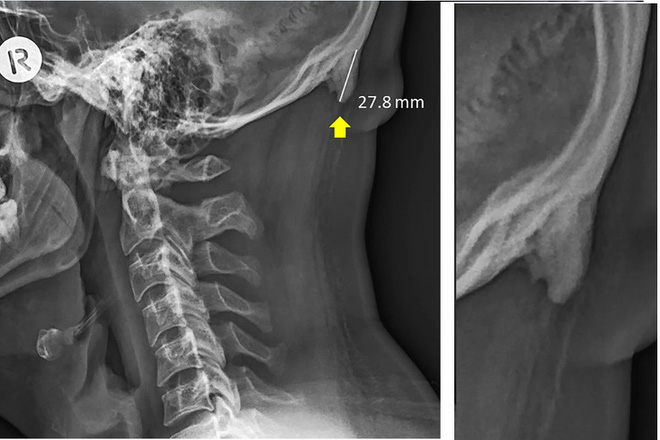

Điểm chung của đa số chúng ta khi sử dụng smartphone, đó là đều có tư thế cúi xuống nhìn màn hình. Chính tư thế này là nguyên nhân gây ra nhiều hội chứng khó chịu liên quan như "cổ nhắn tin" (text-neck, hội chứng ảnh hưởng đến cột sống), ngón cái nhắn tin (texting thumb - do động tác quẹt, lướt màn hình quá nhiều)... Nhưng chưa hết đâu, vào năm 2018 ĐH Sunshine Coast còn chỉ ra một hội chứng kỳ lạ khác trong hộp sọ, đang xảy ra với một bộ phận người trưởng thành hiện nay và có liên quan đến tư thế khi sử dụng smartphone.

Trên thực tế, việc hộp sọ mọc ra những mấu xương với cấu trúc lạ có xảy ra với những người đã qua độ tuổi trung niên. Nhưng theo nghiên cứu của ĐH Sunshine trên hơn 1.200 người trong độ tuổi 18 - 86, thì có đến 1/3 đang xuất hiện mấu xương ở phía sau hộp sọ, với tỷ lệ tăng dần với thanh thiếu niên và người trưởng thành.

Đặc biệt theo nhiều trang tin, các mấu xương này có kết cấu giống như những chiếc sừng, dù không phải sừng. Theo Mark G. L. Sayers - đồng tác giả nghiên cứu, dường như việc này có liên quan đến tần suất sử dụng điện thoại, tablet và các phương tiện điện tử hiện đại khác trong thời gian dài. Tuy nhiên, Sayers cũng cho biết chúng ta vẫn chưa thể kết luận việc dùng điện thoại thực sự là nguyên nhân, mà cần thêm thời gian để khẳng định.

Một trong các giả thuyết được đưa ra là vì tư thế! Khoa học đã chứng minh rằng việc sử dụng một tư thế xấu - như cúi gằm mặt xuống - trong thời gian dài có thể gây ảnh hưởng đến cấu trúc xương. Có lẽ một số người, tư thế ấy đã khiến cột sống cổ bị chịu áp lực quá lớn, dẫn đến việc cơ thể phải tăng thêm xương để hỗ trợ cho quá trình này.